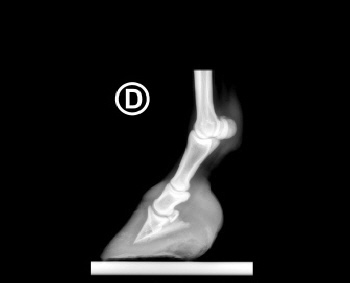

Röntgenbilder akuter- und chronischer Hufrehehufe vorher und nachher

Nachstehend stellen wir einige Röntgenbilder von Hufrehepferden ins Netz, welche das Vorher und das Nachher zeigen. Wir möchten damit aufzeigen, dass durch eine richtige Hufbearbeitung ein Hufbein wieder in eine korrekte Lage innerhalb der Hornkapsel zu liegen kommen kann.

In besonders schweren Fällen wurde doch zumindest eine Optimierung angestrebt.

nachher